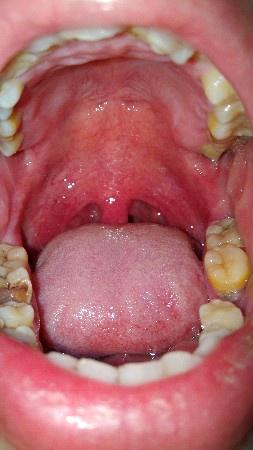

这是智齿冠周炎吗?

最开始左边牙齿最里面的那一颗有些不舒服,而后牙齿周边发疼,现在最里面的肉都非常疼,动嘴就疼。用药酒点了一下,更疼,舌头舔到好像起褶起

用手机开闪光灯拍了一下牙齿。图一图二,这样是智齿冠周炎吗?

顺便拍了一下全口腔,除了蛀牙,掉牙。牙不齐,牙身还好黄,从前就不注意护理牙齿,感觉好自卑了。。。图片都可以拿去教育孩子了。。。